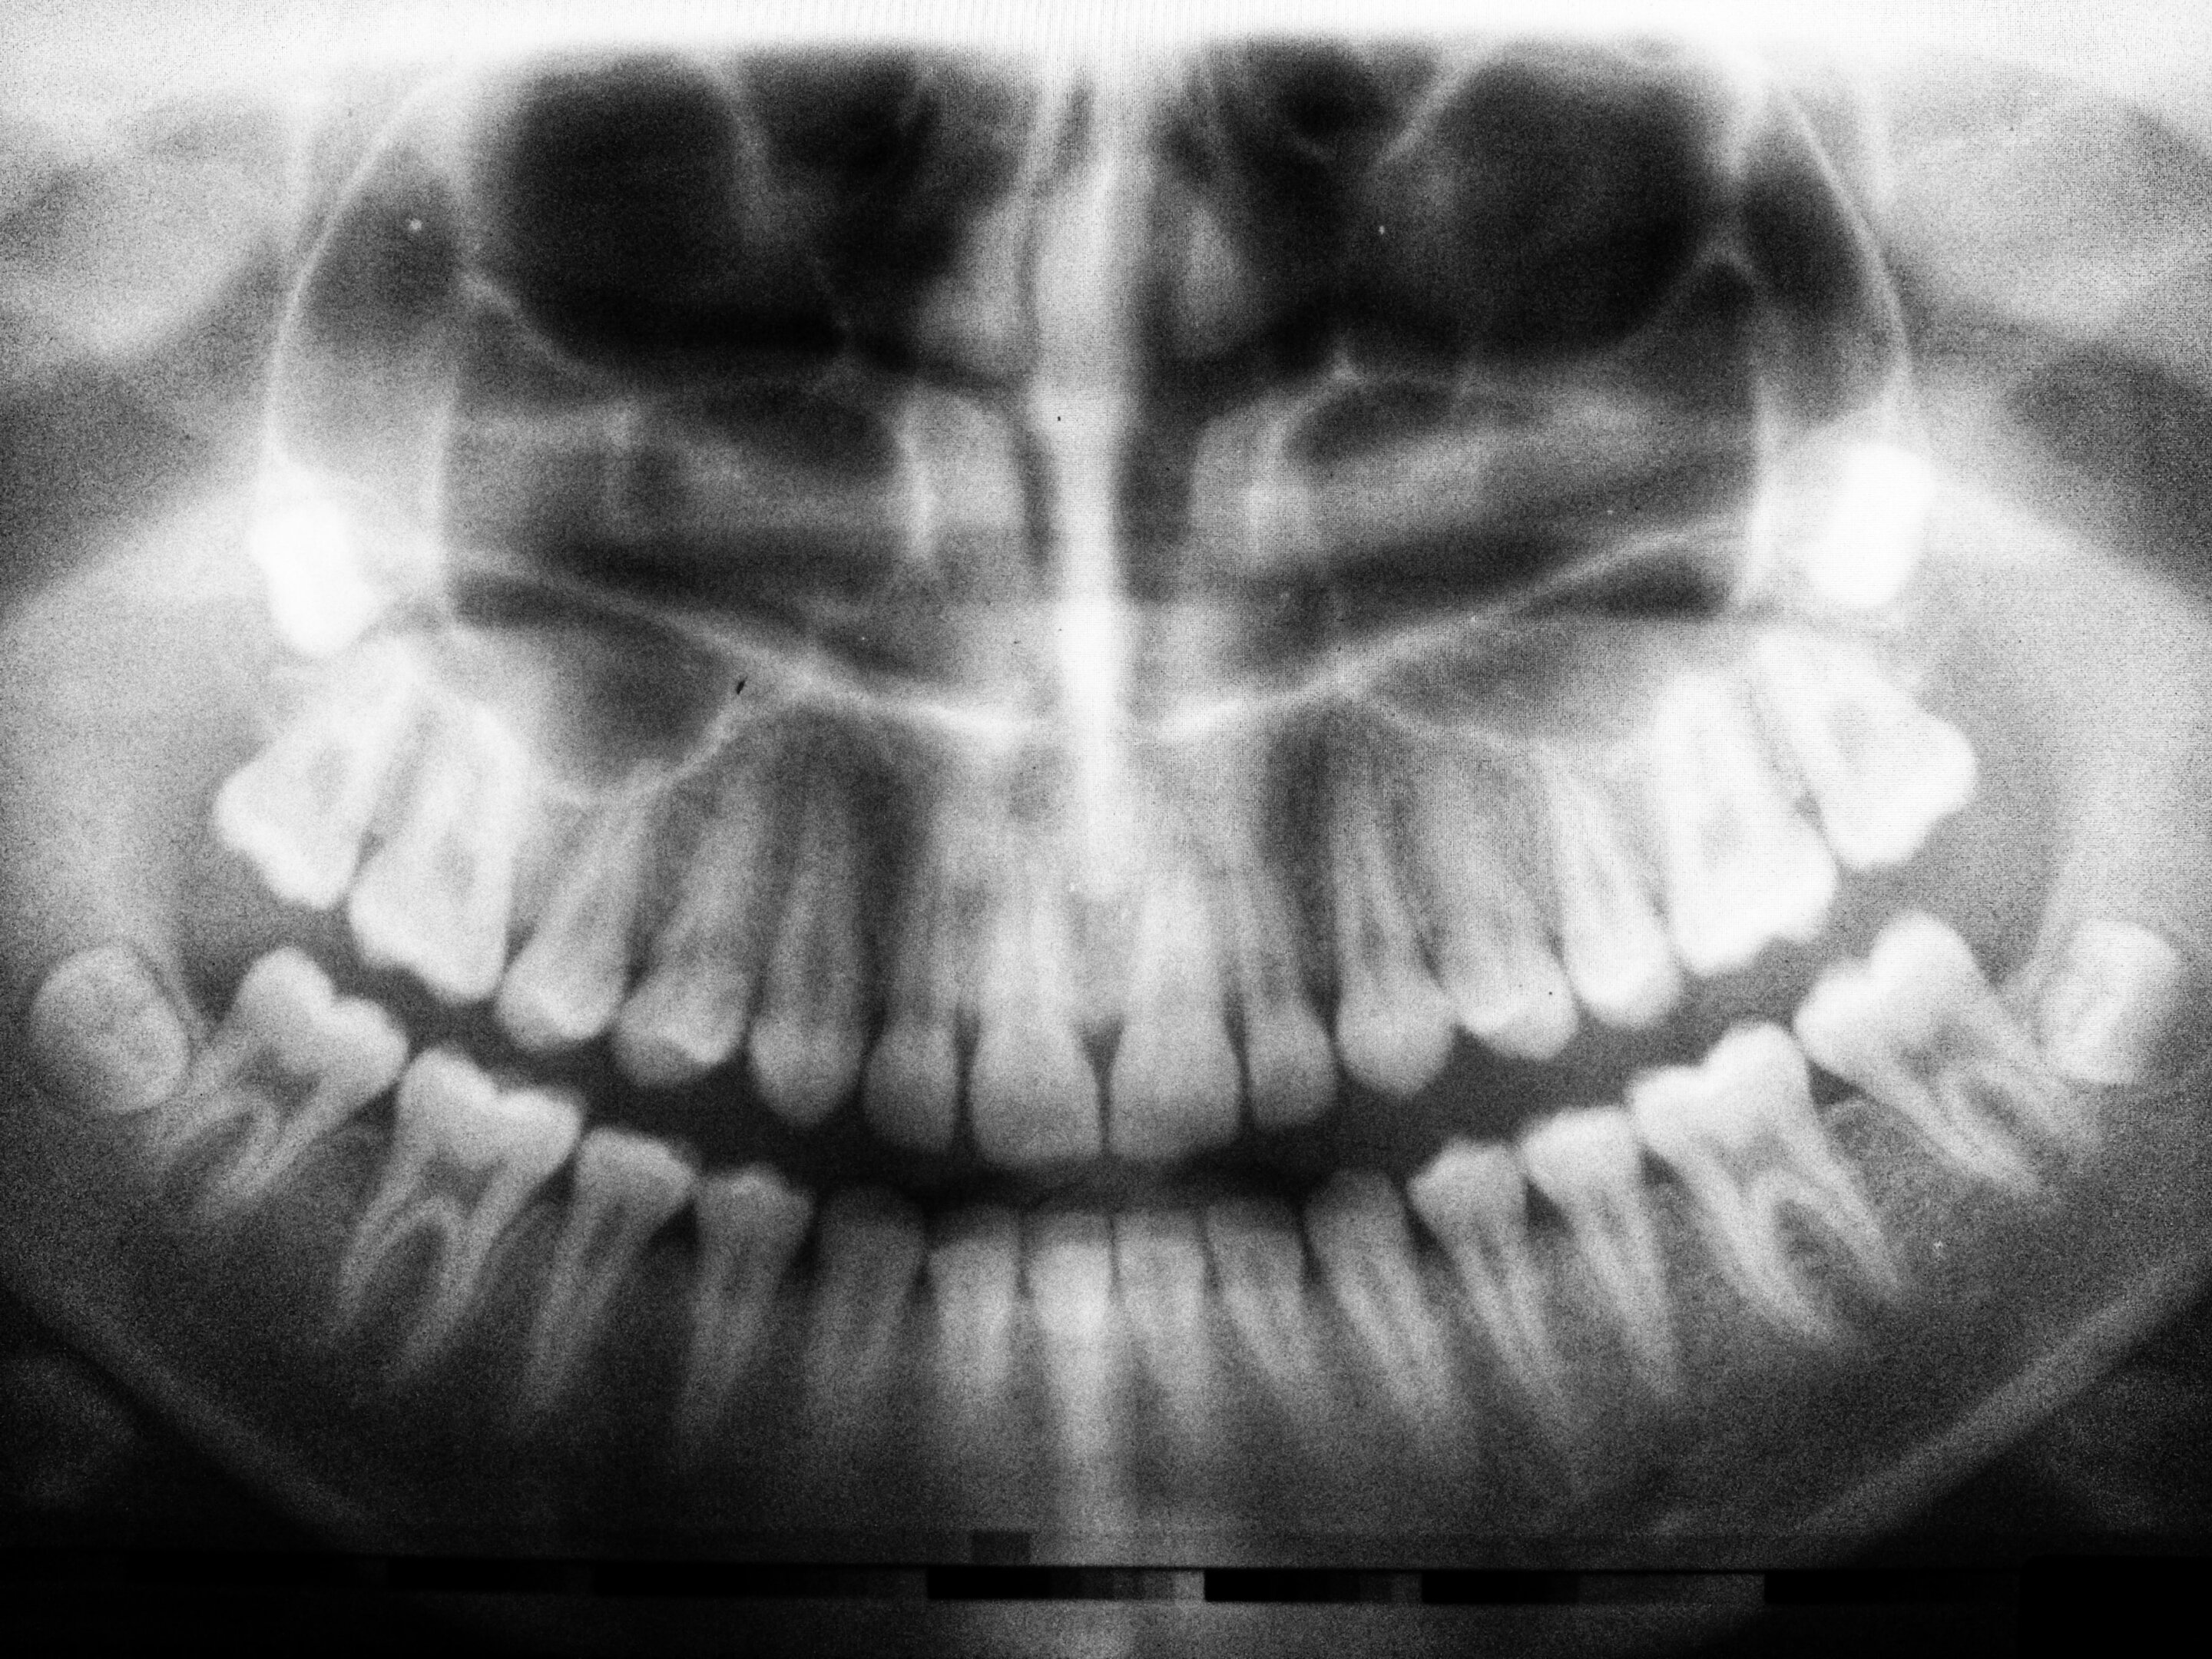

该研究发表在《颅颌骨与睡眠实践》杂志上。研究人员使用一种X射线 - 锥形束计算机断层扫描(CBCT)来测量38名成年参与者的头部和颈部的骨密度,其中一半人有阻塞性睡眠呼吸障碍。当控制了年龄、性别和体重后,患有阻塞性睡眠呼吸暂停的参与者的骨矿物质密度明显低于没有这种情况的参与者。

"如果病人被诊断出患有睡眠呼吸暂停,这可能会影响治疗计划和管理。CBCT成像已经成为日常正畸实践的一个组成部分,可以作为骨矿物质密度低的筛选工具。然后,正畸医生可以告知他们的病人有低骨矿物质密度的倾向,并鼓励他们寻求医生的进一步咨询,以及警告病人可能出现的不良后果、增加的风险和对治疗时间的影响"。